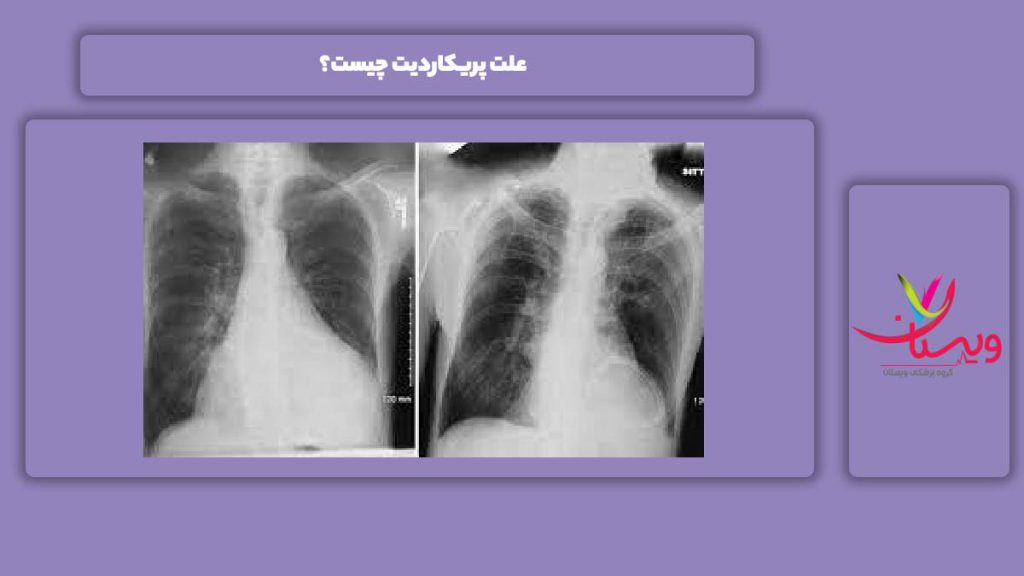

علت پریکاردیت چیست؟

| علت پریکاردیت | توضیح | دستهبندی علت |

| عفونتهای ویروسی | مانند کرونا، آنفلوآنزا، اکوویروس | عفونی |

| بیماریهای خودایمنی | مانند لوپوس و آرتریت روماتوئید | ایمنی |

| ضربه به قفسه سینه | ناشی از تصادف یا جراحی قلب | فیزیکی |

| نارسایی کلیوی | تجمع اوره باعث التهاب پریکارد میشود | متابولیک |

| داروهای خاص | داروهای ضد سرطان یا ضد صرع | دارویی |

پریکاردیت ممکن است به دلایل مختلفی رخ دهد. درک صحیح علتها به تشخیص دقیق و انتخاب بهترین راه درمان پریکاردیت کمک زیادی میکند. این بیماری معمولاً پس از یک عفونت ویروسی یا در پی مشکلات سیستم ایمنی رخ میدهد.